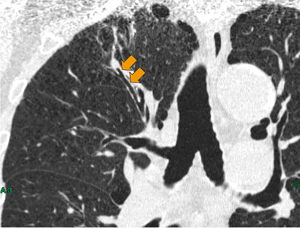

図5 仮想内視鏡表示機能

a:ストレッチCPR

b:仮想内視鏡表示

c:レイサム画像

前項で指摘した通り,CPRの直交断面は検査医師にとって直感的な理解が難しい。しかし現在,新しいバージョンとして直交断面を仮想内視鏡表示に切り替えられる機能が開発され,当院で試験評価中である。この追加機能では,レイサム表示によるナビゲート画像と仮想内視鏡表示を同時に表示することができ,検査医師にとって直感的に受け入れやすい,視覚に訴えるナビゲーション作成が実現できた(図5)。

この追加機能により,病変から逆に気管支の走行を追っていく方法で得たナビゲートの情報を正確に伝えることができるようになった。検査後,「ナビゲーションの通りだった」という検査医師からの言葉は,大変高い評価だと考えられる。

直感的に理解できる仮想内視鏡表示とレイサム画像によるナビゲーションは,検査時間の短縮につながる。このことは,検査医師と何より患者の有益な一助となると考える。したがって,オブリークMPR画像で特定したTBLB検査に適した気管支に鉗子などを誘導するため,仮想内視鏡アプリケーションを利用することは臨床的に有用である。